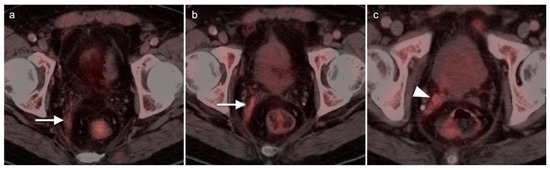

- Scher, B.; Seitz, M.; Reiser, M.; Hungerhuber, E.; Hahn, K.; Tiling, R.; Herzog, P.; Reiser, M.; Schneede, P.; Dresel, S. 18F-FDG PET/CT for staging of penile cancer. J. Nucl. Med. 2005, 46, 1460–1465. [Google Scholar]

- Ottenhof, S.R.; Vegt, E. The role of PET/CT imaging in penile cancer. Transl. Androl. Urol. 2017, 6, 833–838. [Google Scholar] [CrossRef]

- Sadeghi, R.; Gholami, H.; Zakavi, S.R.; Kakhki, V.R.D.; Horenblas, S. Accuracy of 18F-FDG PET/CT for Diagnosing Inguinal Lymph Node Involvement in Penile Squamous Cell Carcinoma. Clin. Nucl. Med. 2012, 37, 436–441. [Google Scholar] [CrossRef]